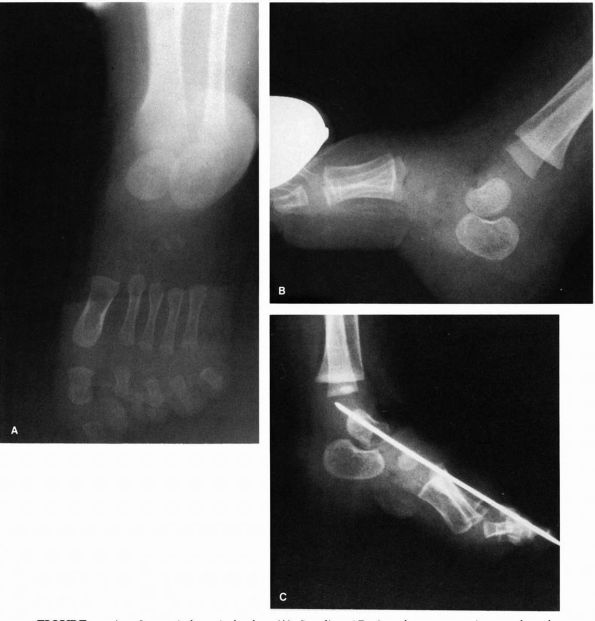

![]() |

FIGURE 20-14. Congenital vertical talus. (A) Standing AP view demonstrates increased angle between talus and calcaneus indicative of the hindfoot valgus. (B) Lateral view of plantar flexion indicates failure of realignment of the metatarsals with the long axis of the talus. (C) Postsurgical realignment of forefoot, midfoot, and hindfoot. (D and E) Standing PA and lateral radiographs 6 years after operation demonstrating restoration of normal anatomic relations.